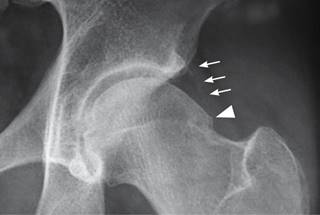

Figura 3: Imagen radiográfica con acercamiento cadera izquierda que muestra: calcificación laminar de cápsula articular en su porción externa (flechas) y osteofito en “giba” en la unión cabeza-cuello (cabeza de flecha).